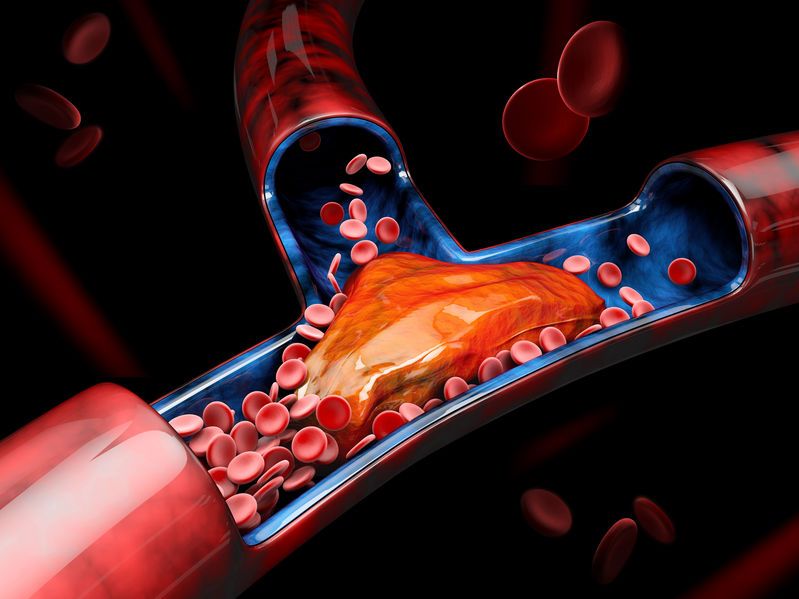

Read ArticleICYMI: Maintain Vigilance for CV Risk Postpartum in Autoimmune Diseases

Pregnant women with autoimmune rheumatic diseases (ARDs) and antiphospholipid syndrome (APS) face significantly increased risks of cardiovascular events (CVEs). This increased risk is often attributed to ARDs, its medications or comorbidities associated with it.